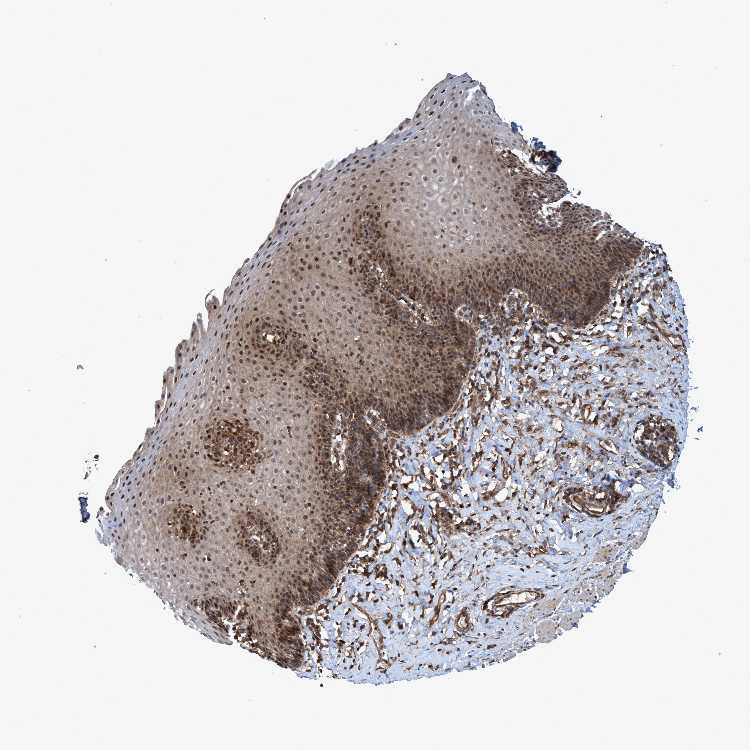

ESOPHAGUS - Antibody stainingi

Antibody staining in the annotated cell types in the current human tissue is reported as not detected, low, medium, or high, based on conventional immunohistochemistry profiling in selected tissues. This score is based on the combination of the staining intensity and fraction of stained cells.

Each image is clickable and will lead to virtual microscopy that enables deeper exploration of all samples and also displays staining intensity scores, fraction scores and subcellular localization as well as patient and tissue information for each sample.

Antibody HPA021425Antibody HPA024423

Squamous epithelial cells MediumHigh